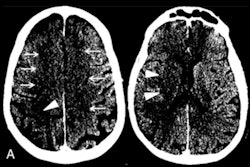

Top image: Chest radiograph of a 23-year-old male with no past medical history who tested positive for COVID-19 via reverse transcription polymerase chain reaction (RT-PCR) and was subsequently discharged from the emergency department with home care and isolation precautions. Portable chest x-ray shows right and left peripheral lower lung zone hazy opacities; total score = 2. Bottom image: Chest radiograph in a 32-year-old overweight (BMI = 30) male positive for COVID-19 with a history of childhood asthma who was subsequently admitted and intubated in the intensive care unit for three days. Portable chest x-ray shows opacities in all three right lung zones and in the left middle and lower lung zones; total score = 5. Images courtesy of Mount Sinai Health System.The study results highlight that COVID-19 findings on chest x-ray can help predict the disease's severity, said senior author Dr. Adam Bernheim in the statement.